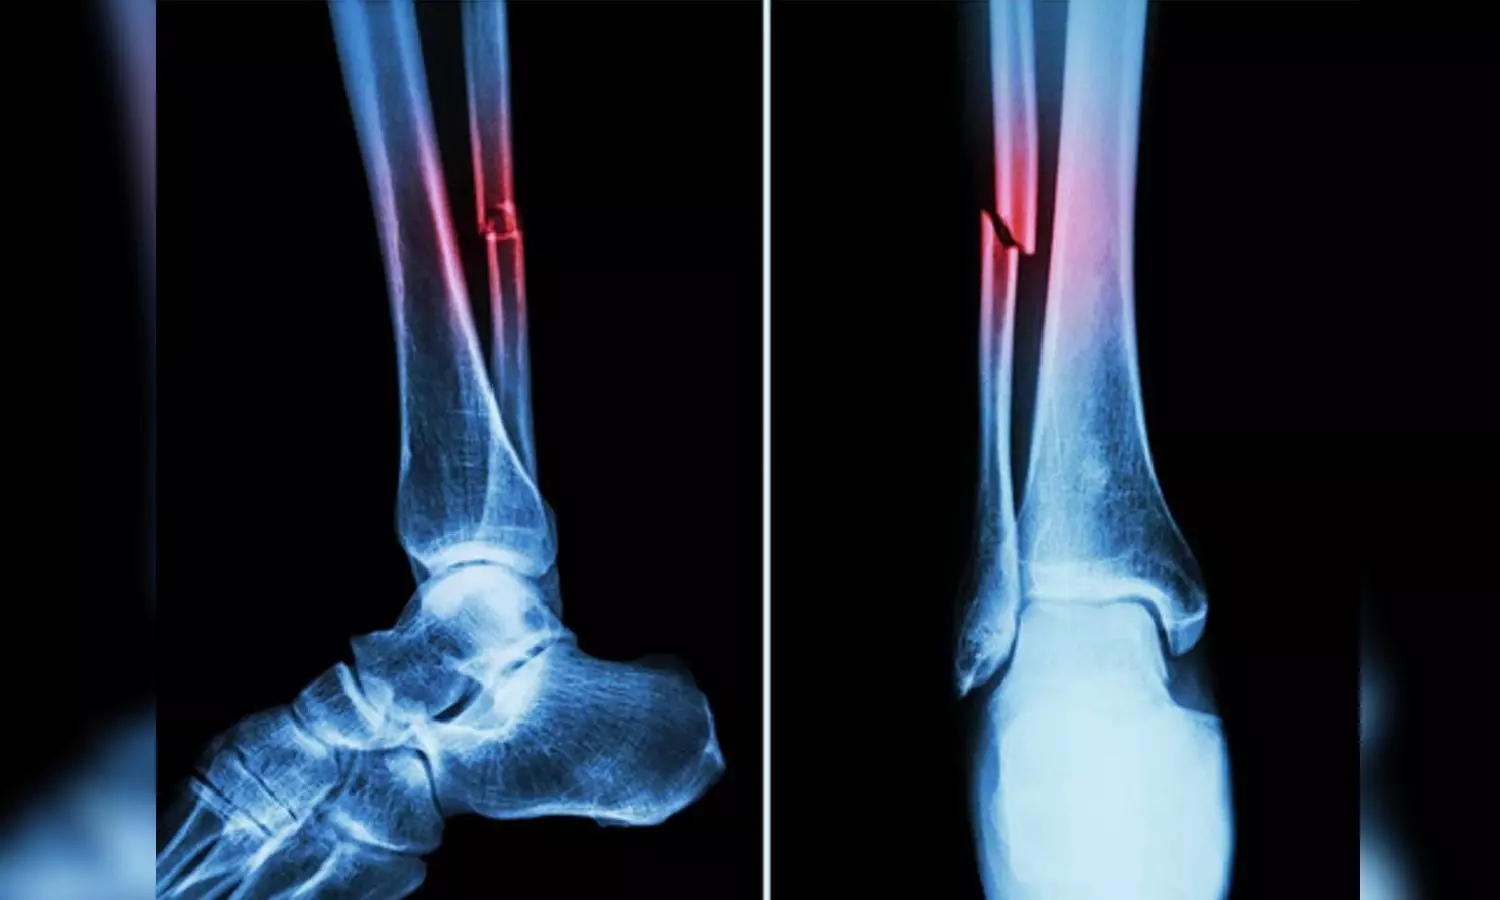

Representative image

In the study, mice who had Covid-19 showed significant bone loss. This loss decreased the bone mechanical strength and increased the risk of fractures.

If similar bone loss occurs in human patients following their Covid‐19 recovery, it could leave them with a long‐term -- even permanent -- increased risk of fractures due to fragile bones. This is especially true in elderly patients.

The study suggested that the higher risk of fragility fractures, when a person falls from standing height or less, may be one of the underreported long-haul symptoms of Covid.